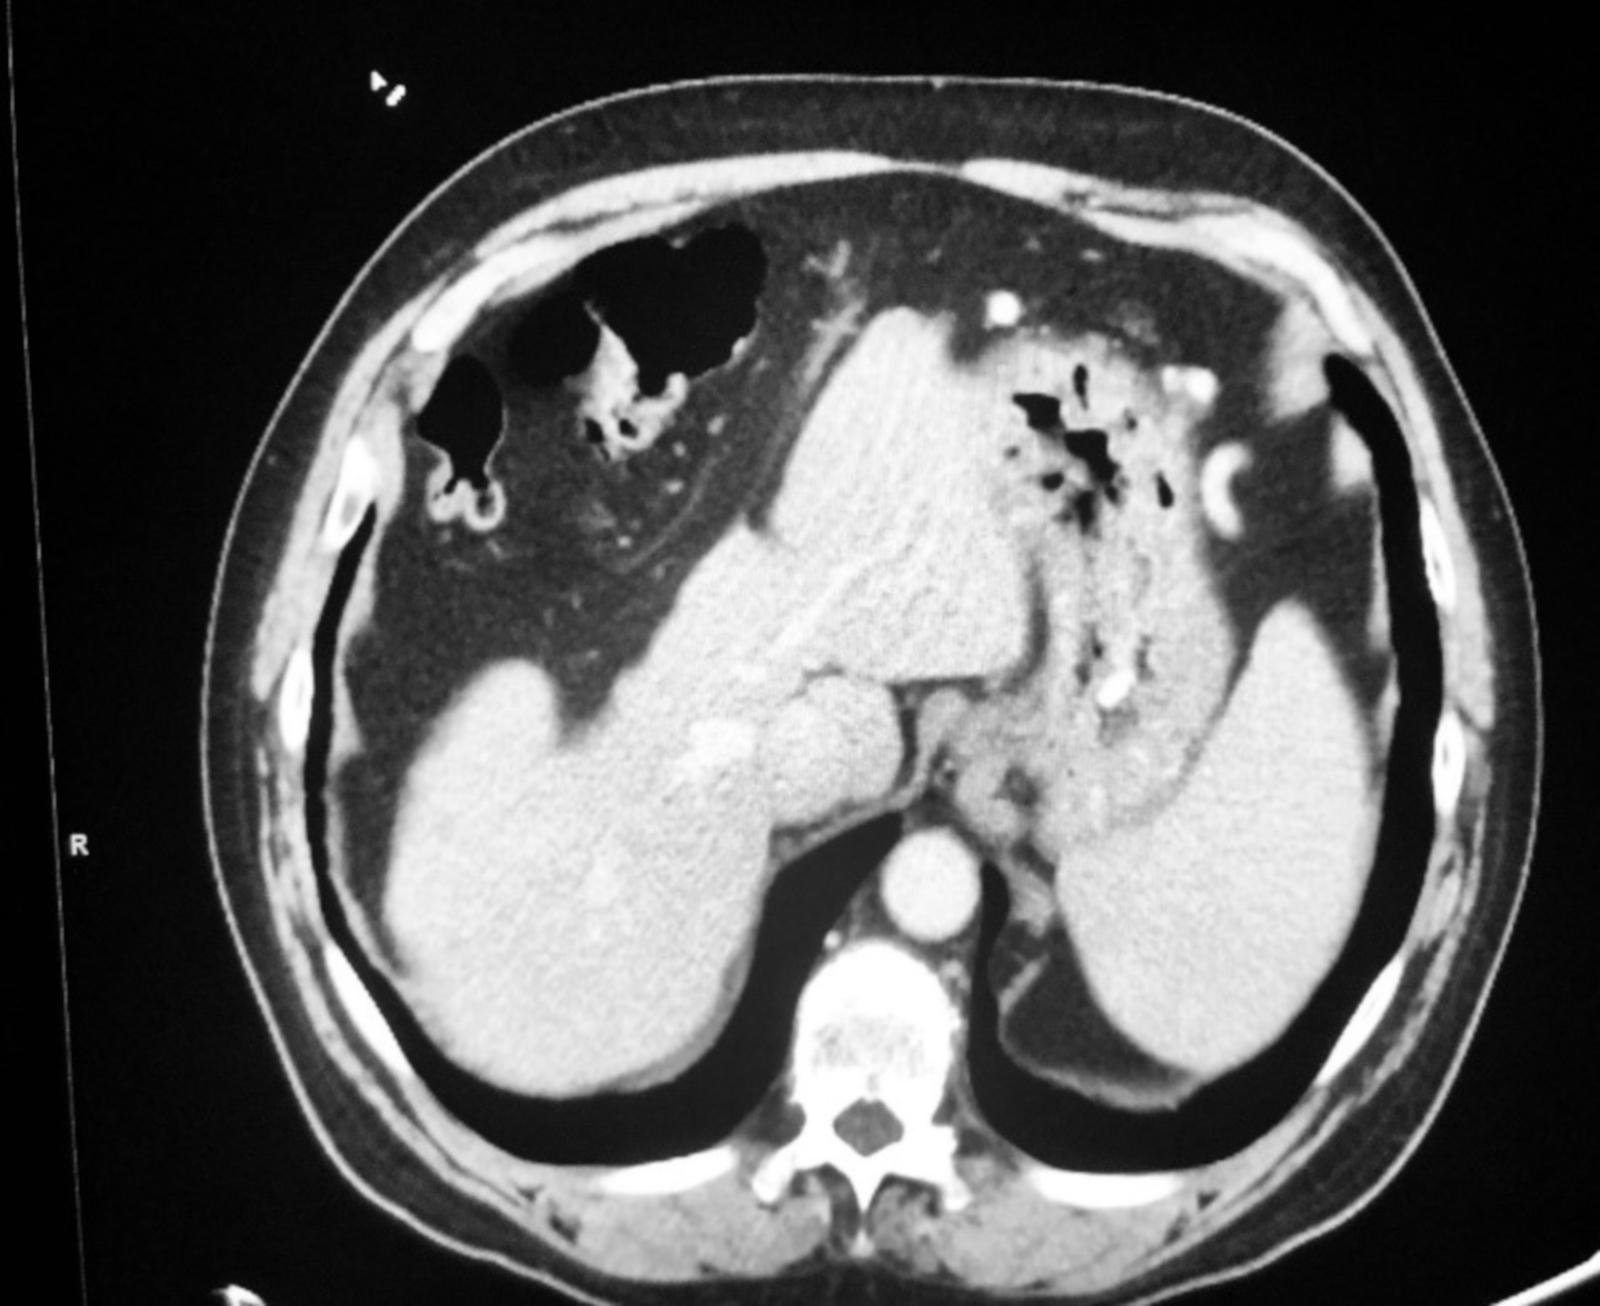

From www.cureus.com

Cureus Streptococcus mitis Abscesses Mimicking Liver Metastases Strep Infection Liver there are more than 120 strains of group a streptococcus bacteria, which is the bacteria that causes group a streptococcal. group b streptococcus (group b strep or gbs) is a bacterium that occurs naturally in the gastrointestinal and genital tracts (vagina, uterus, and. pyogenic liver abscesses usually develops in the context of biliary disease, portal pyemia of. Strep Infection Liver.

Streptococcus mitis Abscesses Mimicking Liver Metastases Cureus Strep Infection Liver the clinical predictors of death during or following infection are advanced. pyogenic liver abscesses usually develops in the context of biliary disease, portal pyemia of various causes,. there are more than 120 strains of group a streptococcus bacteria, which is the bacteria that causes group a streptococcal. streptococcus intermedius is usually found as a solitary isolate.. Strep Infection Liver.